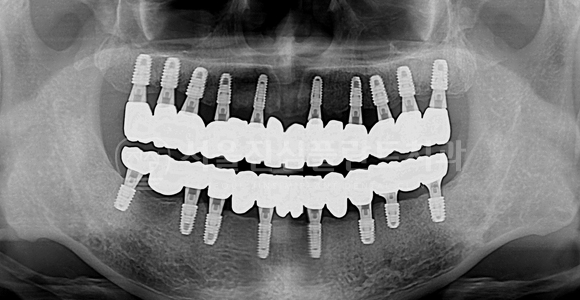

전체 임플란트

BEFORE

AFTER

발치즉시 임플란트 + 전체 임플란트 + 즉시 부하